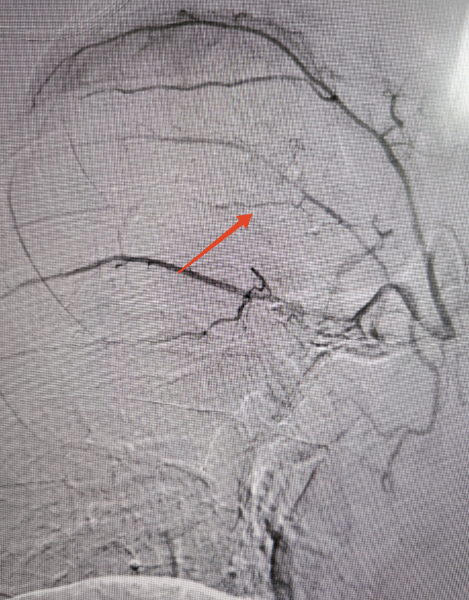

经过多学科讨论,2 月 4 日下午,西安市红会医院介入诊疗中心吴智群教授团队为小伙儿行支气管动脉造影,术中可以看到患者右肺有明显的出血点,给予栓塞后张先生马上不再咯血了。